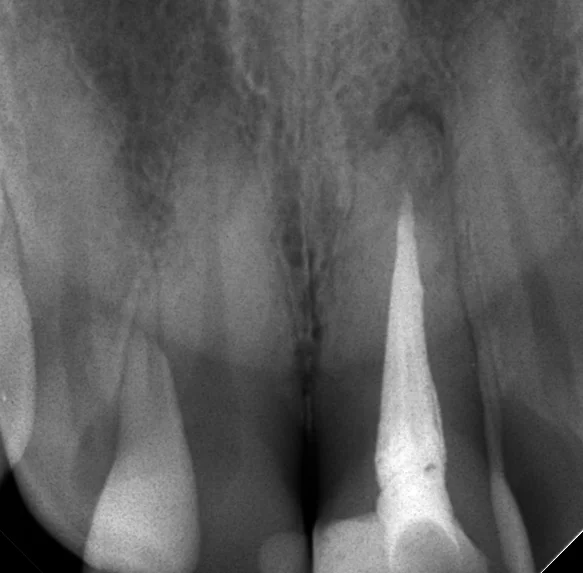

で、この間、口腔内を見た際に1年経過するところだったので、その経過のレントゲンを撮らせて頂きました。

その写真がこちらです。

まだ骨が治りきってはいませんが、大分骨が出来てきていますね!